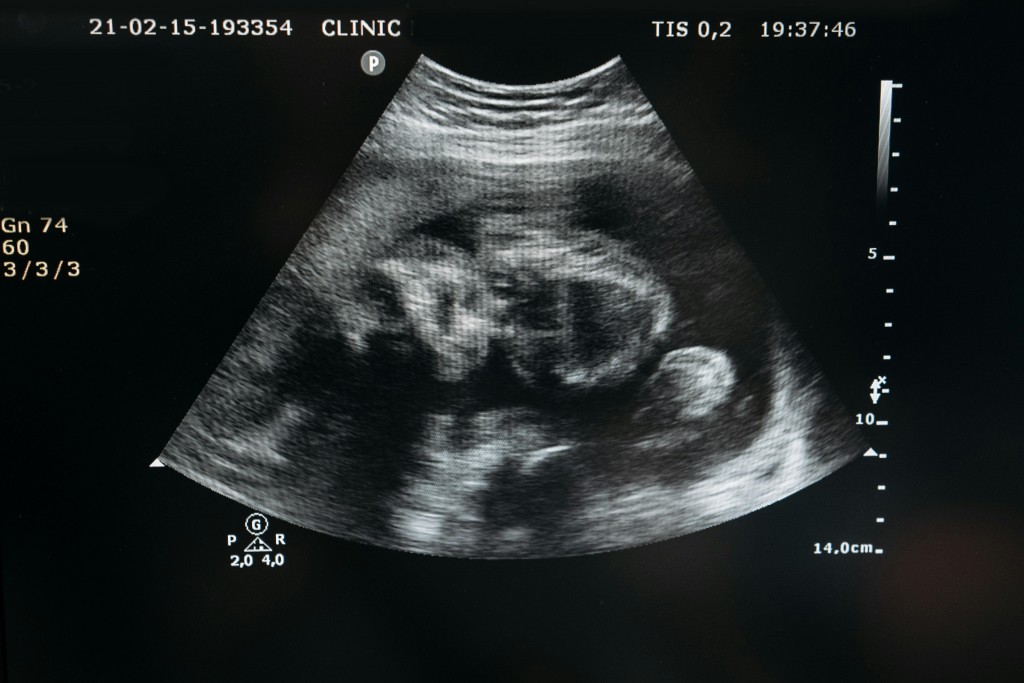

Photo credit: Pavel Danilyuk via Pexels. Article by Paige Bennett. EcoWatch – January 31, 2025.

A new study presented as part of the annual Society for Maternal-Fetal Medicine meeting has revealed a link between microplastic bioaccumulation in the human placenta to preterm, or premature, births. In the study, researchers analyzed 175 placentas collected at both term and preterm, or under 37 weeks of pregnancy, and measured the amounts of 12 different […]